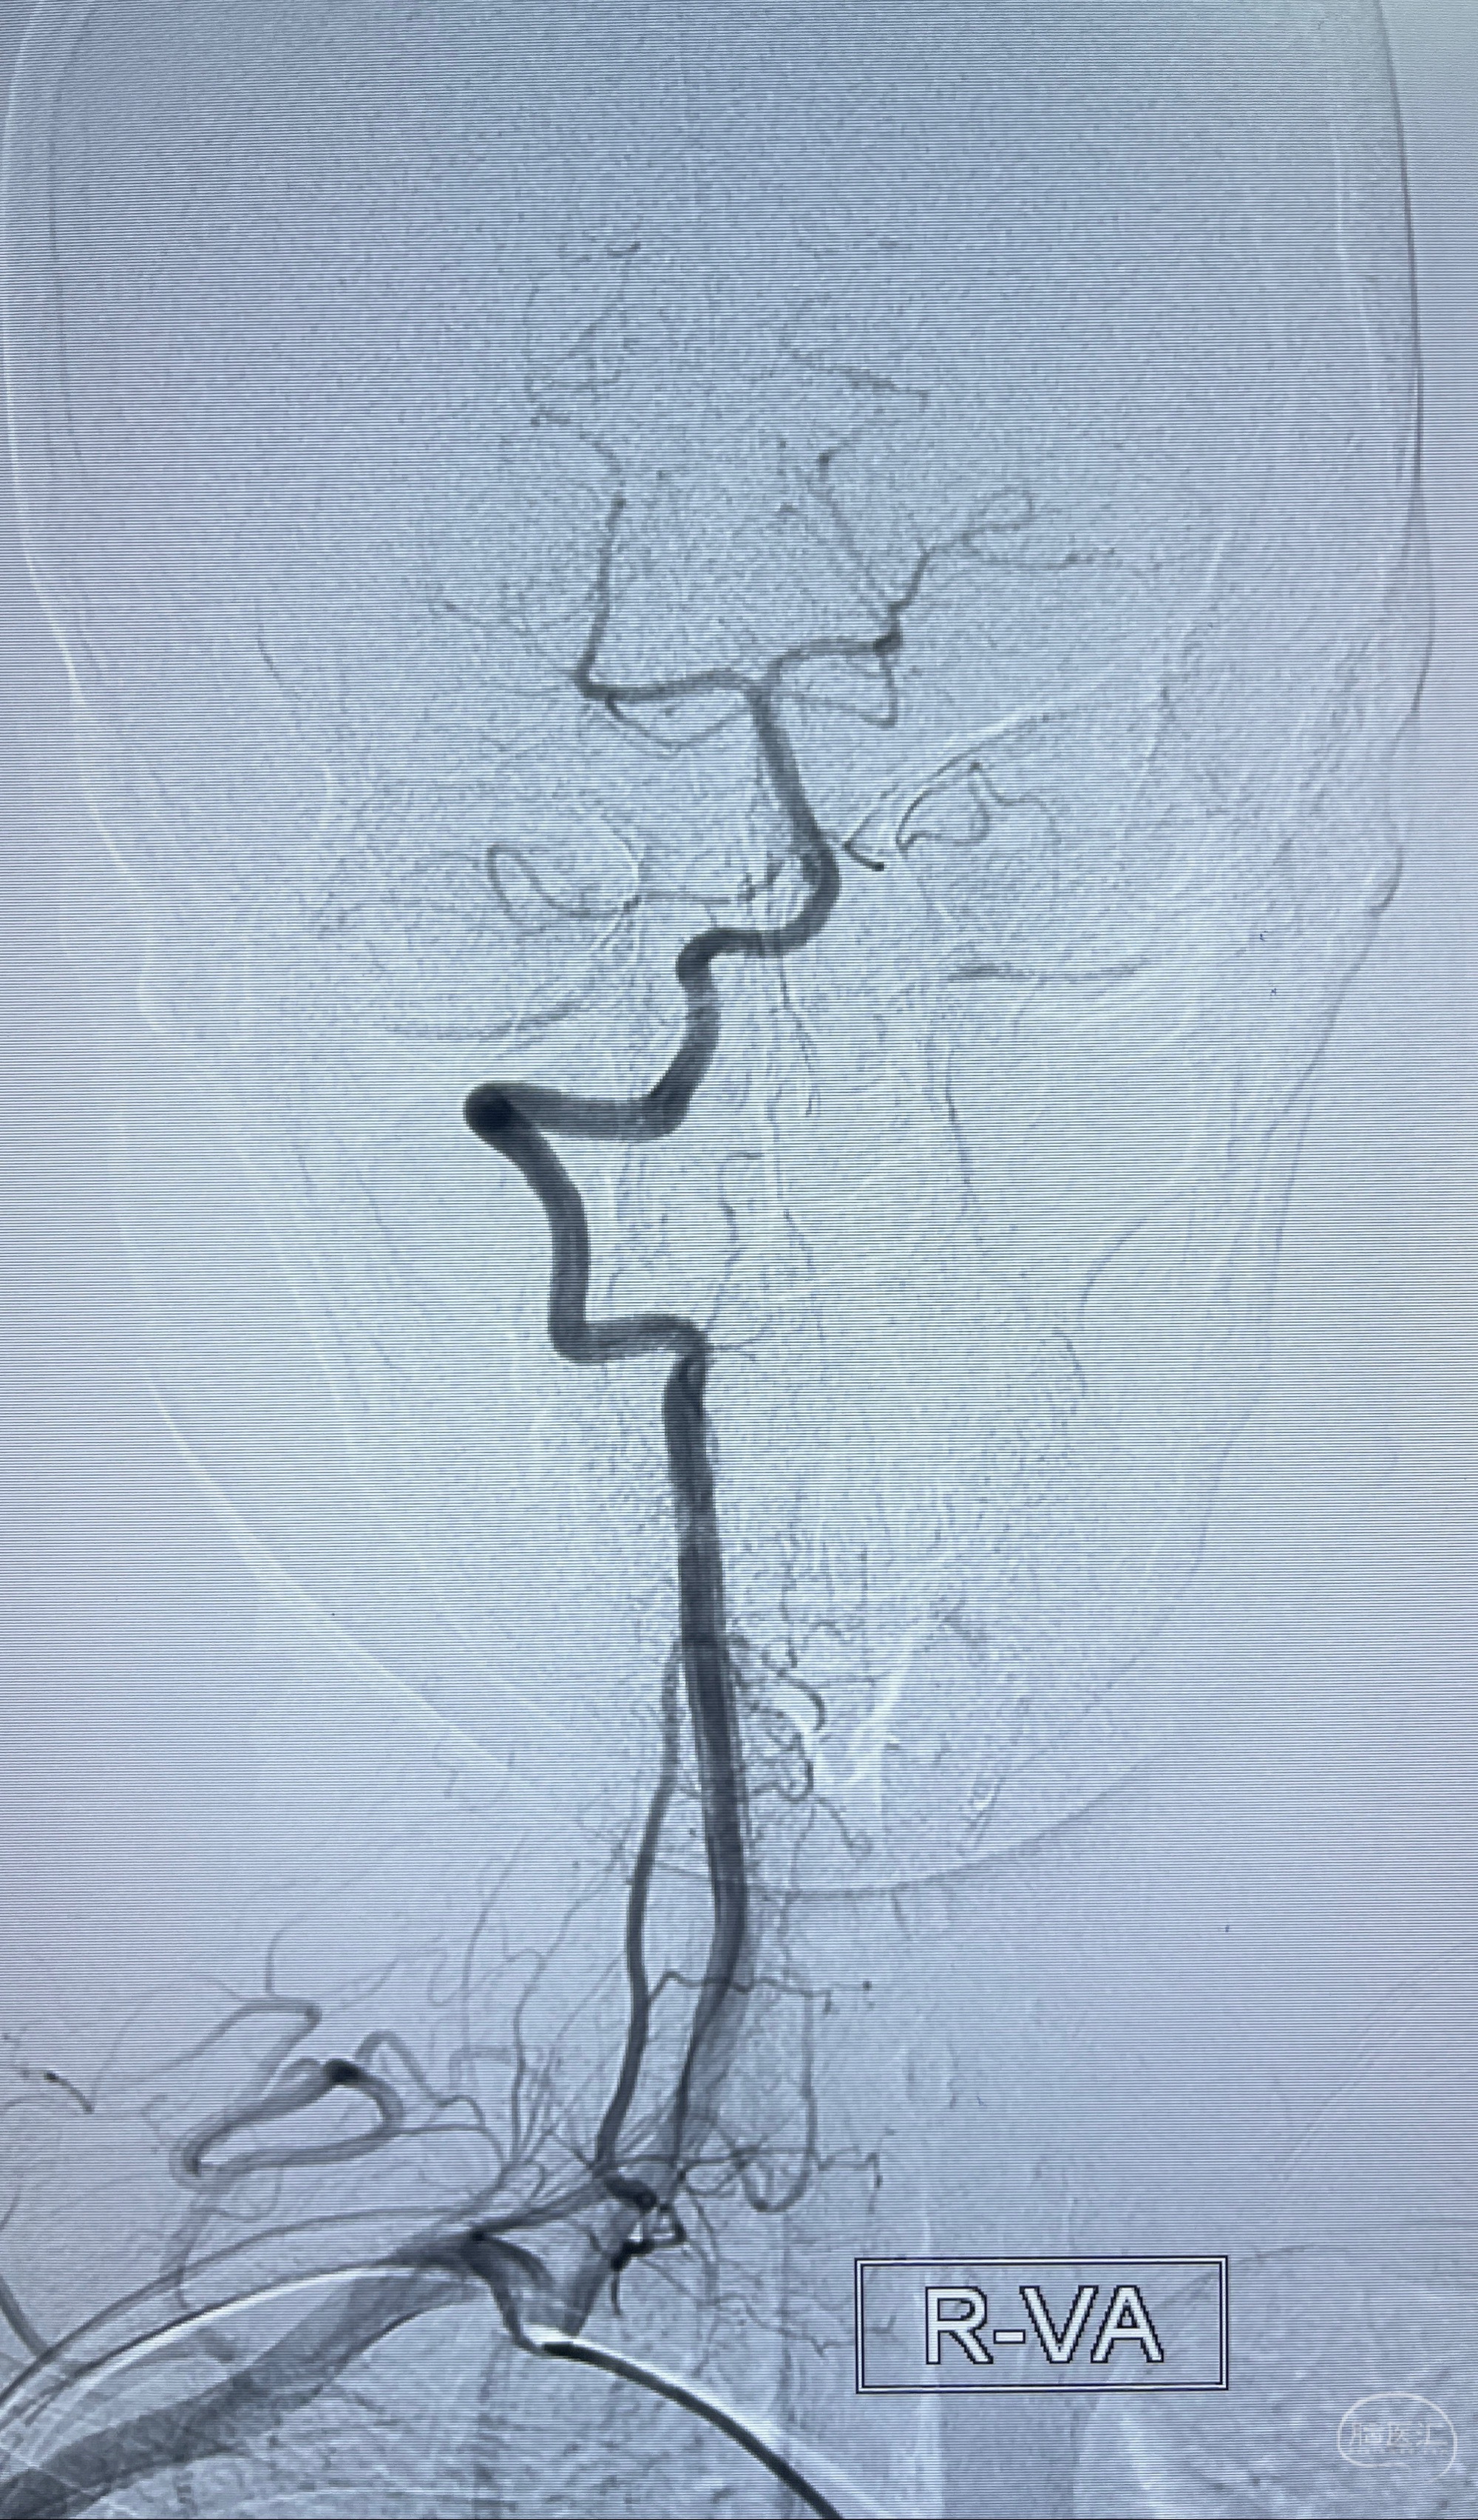

现病史:患者2023-07-12体检时头颅MRI提示:左侧大脑中动脉可疑病灶,遂于上海大学附属第三医院查头颅CTA提示:左侧大脑中动脉M1段动脉瘤,右侧大脑前动脉A1段缺如,左侧椎动脉V4段纤细。追问既往病史,患者诉十余年来睡眠不佳,反复头痛,偶有视物模糊,服用佐匹克隆、维生素B1、谷维素、刺五加片治疗,睡眠有改善。现患者有头痛不适,为求进一步诊疗左侧大脑中动脉M1段动脉瘤至我科就诊,收治入院。

辅助检查:2023-07-12 上海大学附属第三医院 头颅CTA:左侧大脑中动脉M1段动脉瘤(1.7*3.4mm),右侧大脑前动脉A1段缺如,左侧椎动脉V4段纤细。

2023-08-14DSA: